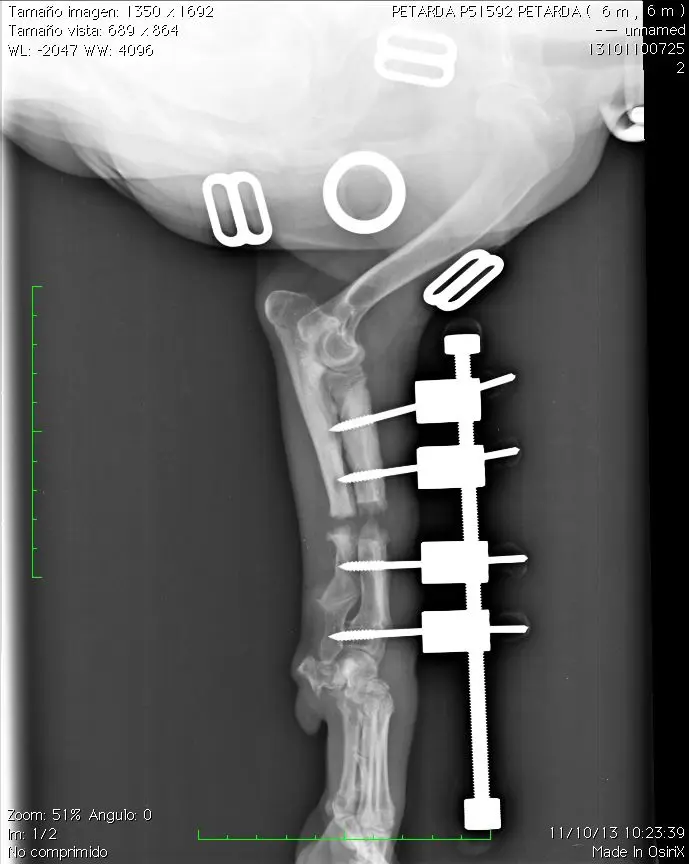

Caso 1

Petarda, beagle, hembra, 5 meses.

Cierre prematuro epífisis distal del radio. Incongruencia codo. Poca desviación de la extremidad

Deben realizarse radiografías semanalmente para comprobar que la distracción es efectiva

16-11-13 Cuando ambas extremidades tienen la misma longitud finalizamos la distracción aunque podemos continuar unos mm mas ya que la extremidad no afectada continuará su crecimiento. Muchos perros de unos 15 kg toleran discrepancia de 2 cm o más entre ambas extremidades sin sintomatología

Aspecto del hueso el 9-12-13. Observese la perfecta congruencia articular del codo. La articulación carporadial está anquilosada pero no presenta dolor